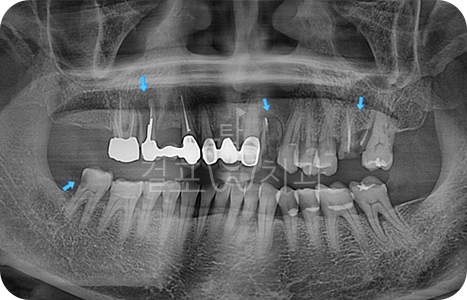

Before

After

• 자연치아를 최대한 보존하면서 꼭 필요한 부분만 임플란트를 식립하였습니다. 광범위한 뼈이식이 필요하였으며 오염되었던 치근 주위로 뼈를 만들어 내야하는 고난도 케이스입니다.

치유가 아직 덜된 발치 부위에 상악동 수술과 3면 뼈이식이 들어가는 고난도 치료였으나 큰 문제 없이 이상적으로 치료되었습니다.